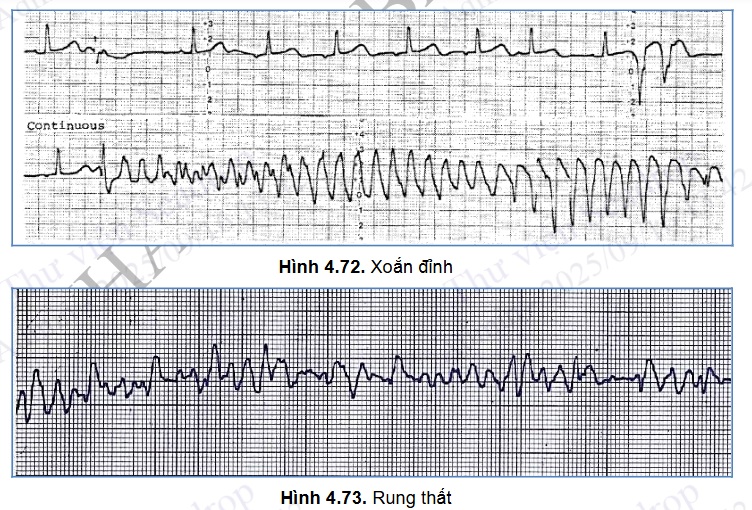

Cuồng thất: điện tâm đồ về cơ bản giống tim nhanh thất nhưng tần số tim rất nhanh > 300 ck/phút.

Xoắn đỉnh: phức bộ QRS giãn rộng, đa hình thái, trục QRS liên tục thay đổi, dường như xoắn quanh đường đẳng điện.

Rung thất: các sóng P, Q, R, S, T biến mất, thay bằng các sóng rung (f) to nhỏ, ngoằn ngoèo trên điện tâm đồ.